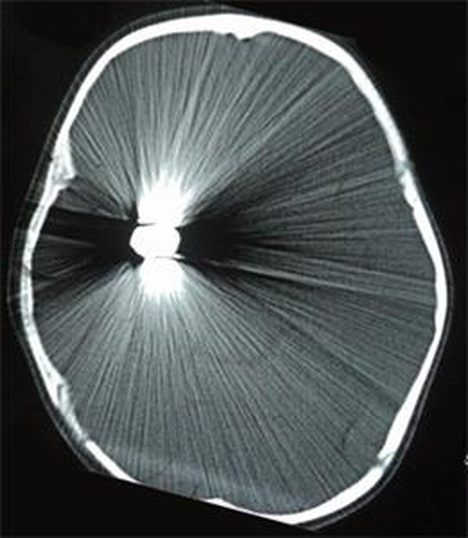

A buried artefact

Sometimes there is an accidental beauty in the most macabre of events. Having a bullet lodged in your brain can produce beautiful CT scans due to the scanner’s difficulty with imaging metal objects.

The scan is from an 8-year-old girl who was hit by a bullet that was fired into the air in celebration. She was reportedly fine but this scan is from her hospital admission.

This pattern is an unintended consequence. It’s called a ‘streak’ or ‘star’ artefact and is caused by a combination of the CT scanner beam being over-absorbed by the dense metal object and the image construction software not being able to make sense of the incoming information correctly.

There’s various other images online if you want more unintended brain glitter.